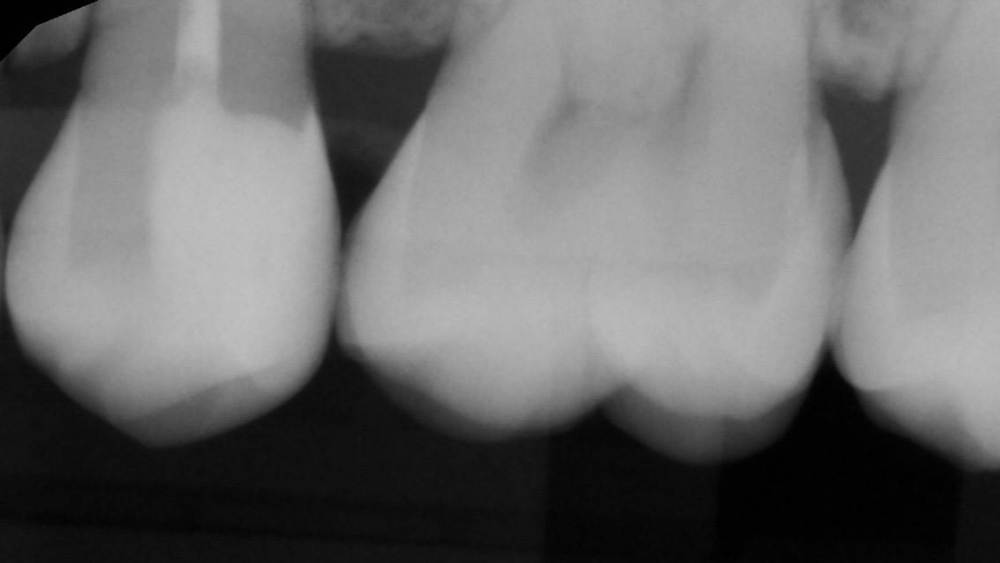

Гарриевич Опубликовано 6 апреля, 2023 Автор Поделиться Опубликовано 6 апреля, 2023 3 1 Ссылка на комментарий

Doc Опубликовано 7 апреля, 2023 Поделиться Опубликовано 7 апреля, 2023 Удивительное рядом. 1 Ссылка на комментарий

Гарриевич Опубликовано 7 апреля, 2023 Автор Поделиться Опубликовано 7 апреля, 2023 5 часов назад, Doc сказал: Удивительное рядом. Хейтеры скажут фотошоп Ссылка на комментарий

Doc Опубликовано 8 апреля, 2023 Поделиться Опубликовано 8 апреля, 2023 19 часов назад, Гарриевич сказал: Хейтеры скажут фотошоп Не, я не скажу. Первый раз про такое я лет 20 назад слушал лекцию. Наш Арком привозил какого-то лектора из Америки. Тогда очень удивлялся, помню. Но потом регулярно эта методика где-то всплывала, хоть и очень-очень редко. Сам не стал бы так рисковать, наверное. Хотя бы потому, что не уверен, что в суде потом можно отбиться от обвинения в некачественной пломбировке канала. :))) Ссылка на комментарий

Гарриевич Опубликовано 8 апреля, 2023 Автор Поделиться Опубликовано 8 апреля, 2023 6 часов назад, Kolchanov сказал: И сам заработал и неизвестному коллеге-ретритчику помог. А я чего вообще кто то может решить туда лезть?) с виду отличный зуб)) Ссылка на комментарий